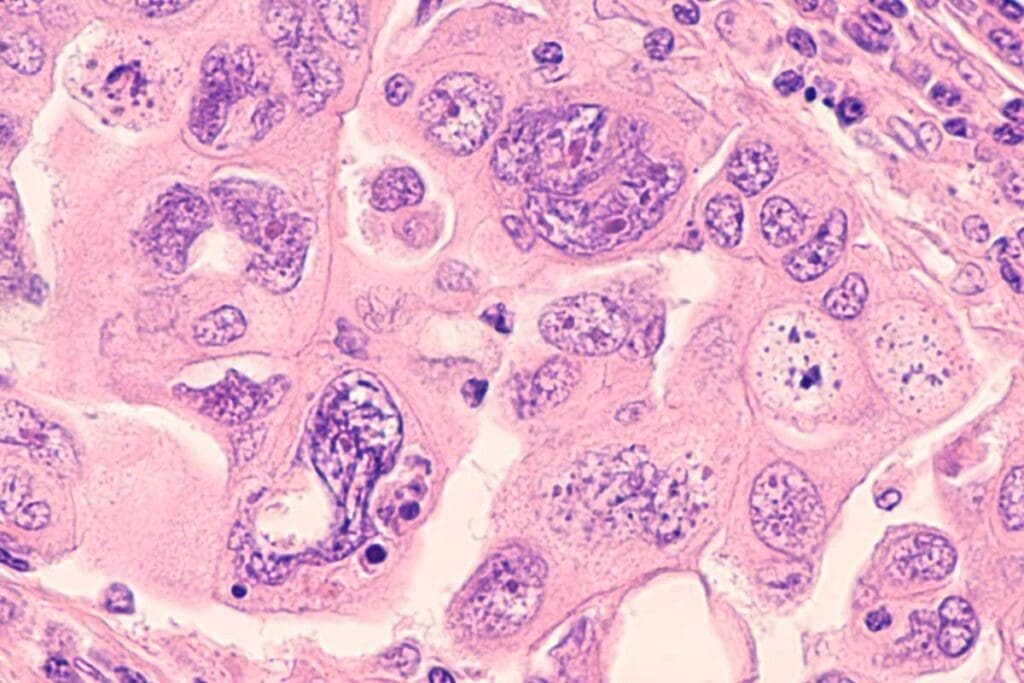

Adenocarcinomas

Adenocarcinomas start in glandular tissue. They are common in places like the breast, prostate, colon, and pancreas. They are known for forming gland-like structures.

Breast adenocarcinoma is a common breast cancer. It starts in the milk ducts or lobules. Treatment depends on where and how far the cancer has spread.